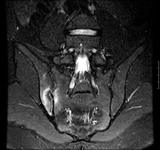

Plain radiograph showing bilateral sacroiliitis in a patient with ankylosing spondylitis

BMJ 2006;333;581-585. © BMJ Publishing Group Ltd 2009